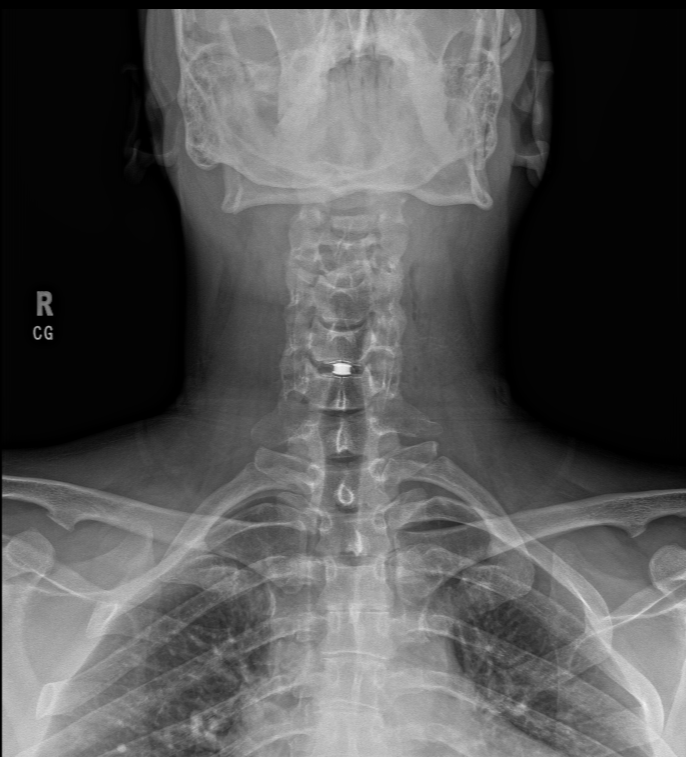

Anterior Cervical Disc Replacement